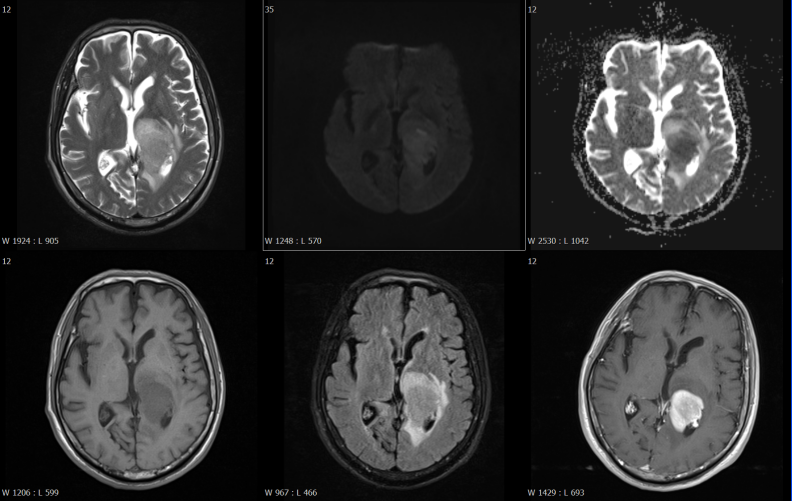

磁共振檢查方面,開展了高技術(shù)的增強(qiáng)掃描動態(tài)分析,動態(tài)灌注掃描、波譜分析,為腫瘤鑒別提供了有效方法,比如腦內(nèi)膠質(zhì)瘤、淋巴瘤的鑒別。

乏血供病變---淋巴瘤